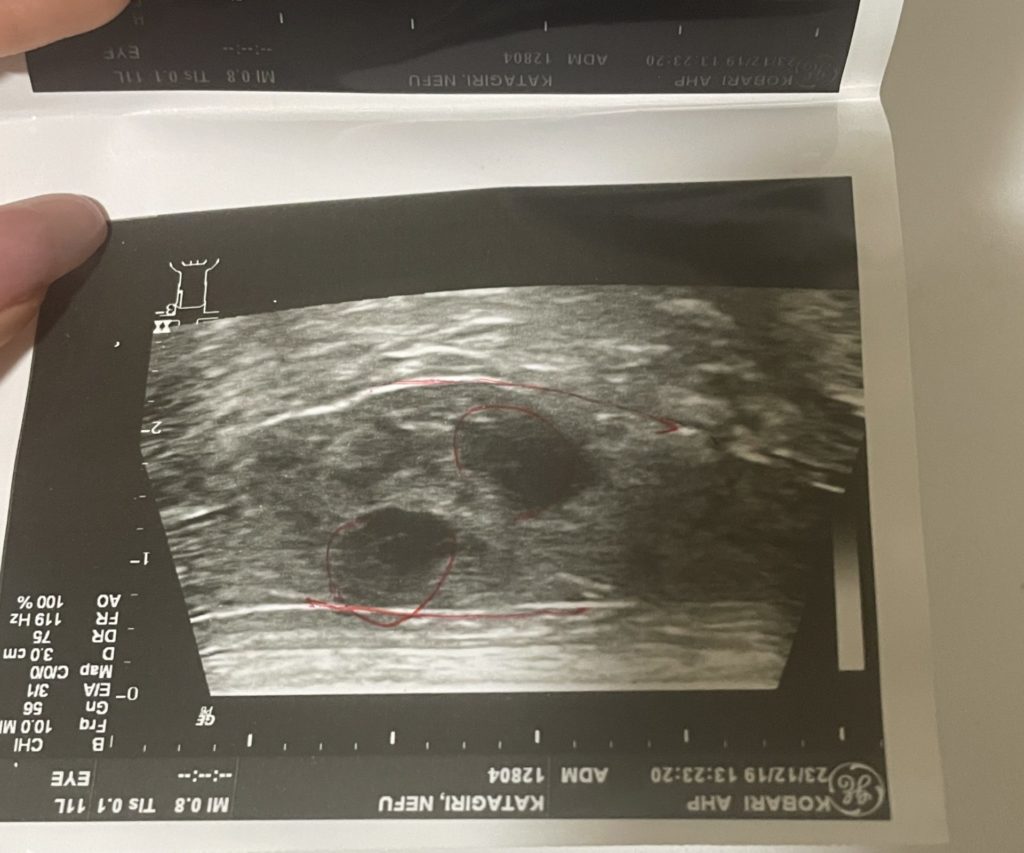

脾臓の腫瘍が脾臓からはみ出る大きさになり、悪性、良性に関わらず、

はみ出ているといつ破裂するかわからず

破裂したら脾臓摘出手術を早急にすることになった話でした。

2023年の12月19日にがん専門の病院で再度検査を受けたら

良性だったとしてもやはり脾臓からはみ出しているから、破裂したら命に関わる。

先生による脾臓の説明

ネフの腫瘍